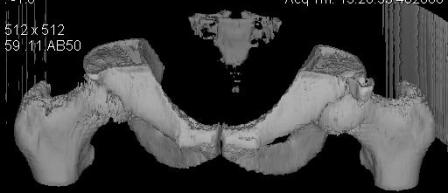

Уважаемые коллеги! Хотелось бы услышать ваше мнение. Мужчина 50л поступил с переломами костей таза. Закрытый перелом крыла подвздошной кости, переднего края вертлужной впадины справа.

Достаточно ли консервативного лечения, стоит ли беспокоиться о переднем крае? В приложении КТ.